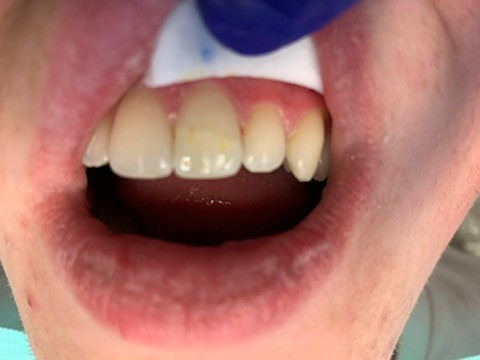

13

Anterior chipped tooth repair.